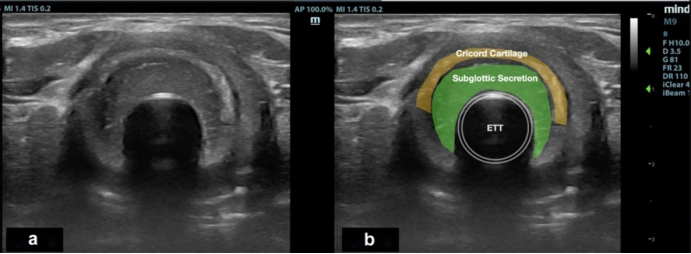

通过CT可观察到气囊上区域的高密度影与液平(图1),超声检查也可直观评估滞留物的存在和量(图2),为临床干预提供影像学依据。

图片

1  CT下观察气囊上滞留物

2  超声评估气囊上滞留物